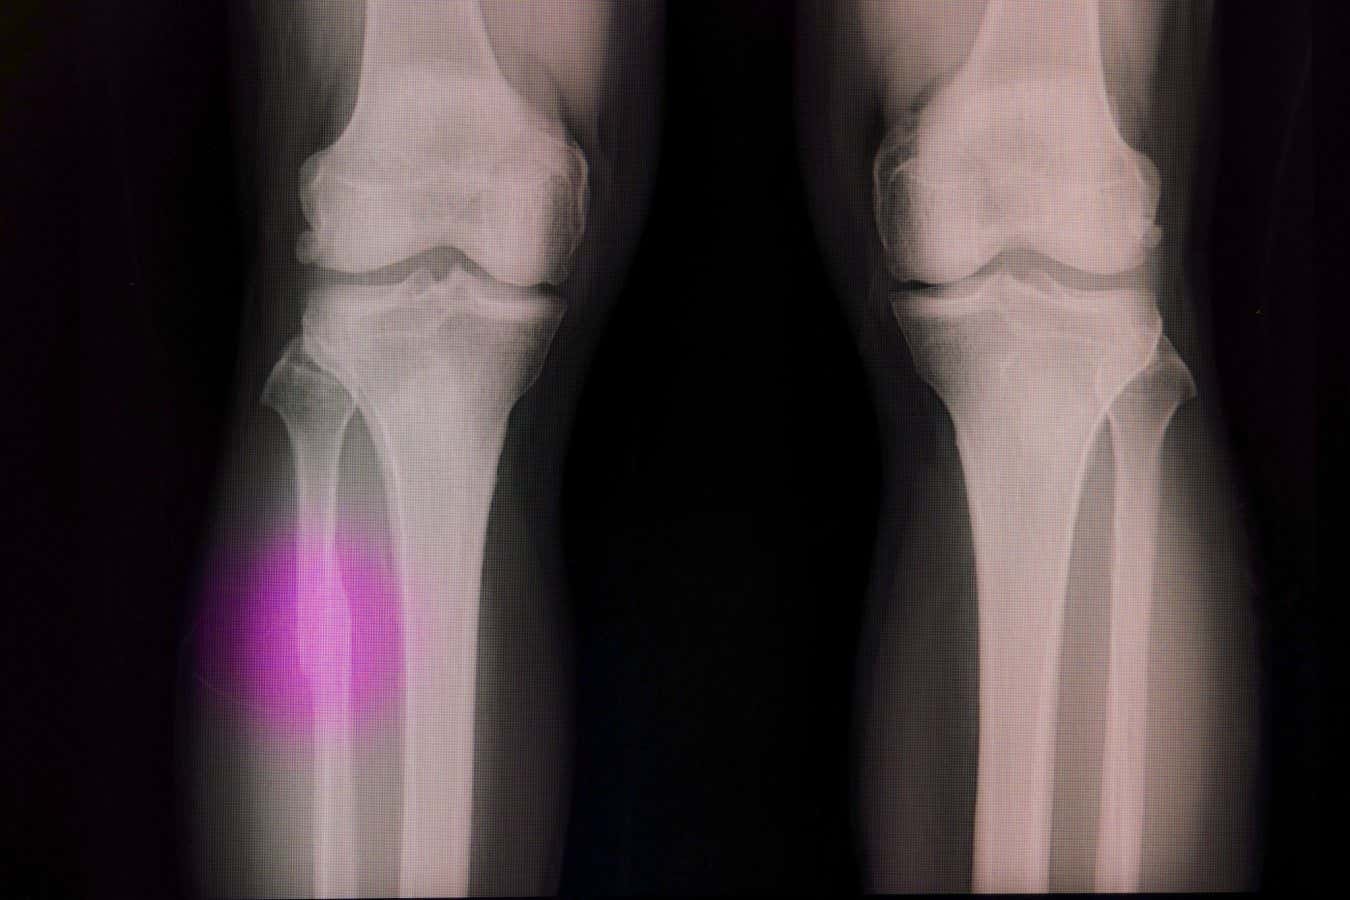

Broken bones often need a material to fill the void

Sopone Nawoot/Alamy